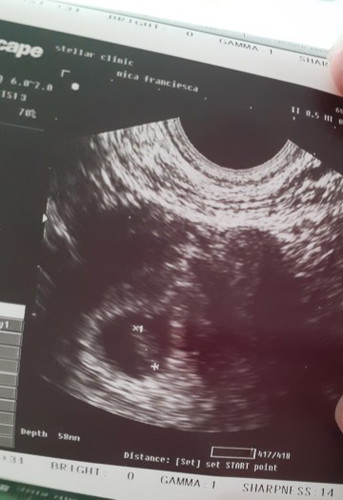

7 weeks or 9 weeks??

Ang bilang ko 9weeks pero sa size daw sabi nung nag transV utz saken 7weeks palang daw. ? Btw, Aug 28 yung last mens ko.